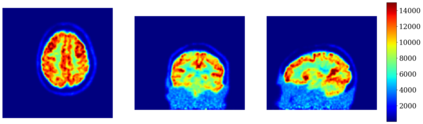

In this work, we investigate hybrid PET reconstruction algorithms based on coupling a model-based variational reconstruction and the application of a separately learnt Deep Neural Network operator (DNN) in an ADMM Plug and Play framework. Following recent results in optimization, fixed point convergence of the scheme can be achieved by enforcing an additional constraint on network parameters during learning. We propose such an ADMM algorithm and show in a realistic [18F]-FDG synthetic brain exam that the proposed scheme indeed lead experimentally to convergence to a meaningful fixed point. When the proposed constraint is not enforced during learning of the DNN, the proposed ADMM algorithm was observed experimentally not to converge.